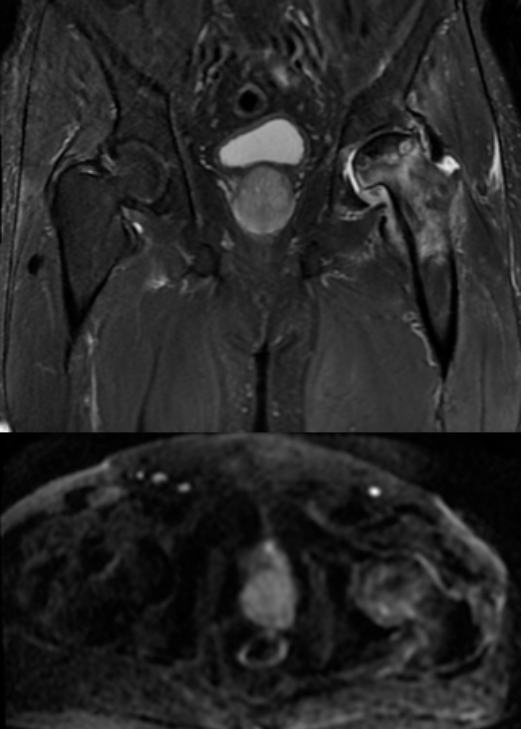

MRI结果显示,王先生的左侧股骨头已经变扁,出现局部塌陷。

左侧股骨头变扁,局部塌陷,骨质内见线状T1WI低信号,髋臼及股骨近端骨松质见片状T1WI低、T2WI压脂高信号,DWI高信号,周围滑膜增厚,邻近软组织肿胀,PD压脂信号增高,关节腔少量积液。

多序列、多参数成像:如同本例中运用的T1WI、T2WI压脂、DWI、PD压脂等不同序列,能从血流、水分、细胞密度等多个维度评估病变性质,为医生提供全面的诊断信息。